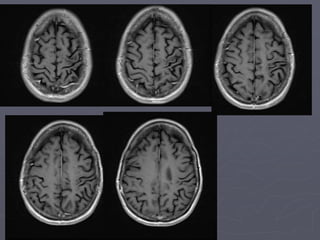

► Jan 2013 – May 2013: worsening spasticity

right arm and leg

 intensive physio

 antispasmodics and botox

 Walking distance decreasing (200m then drags

leg)

 Attempting to go back to work

 No MS related activity on MRI (or clinically)

Jan 2013